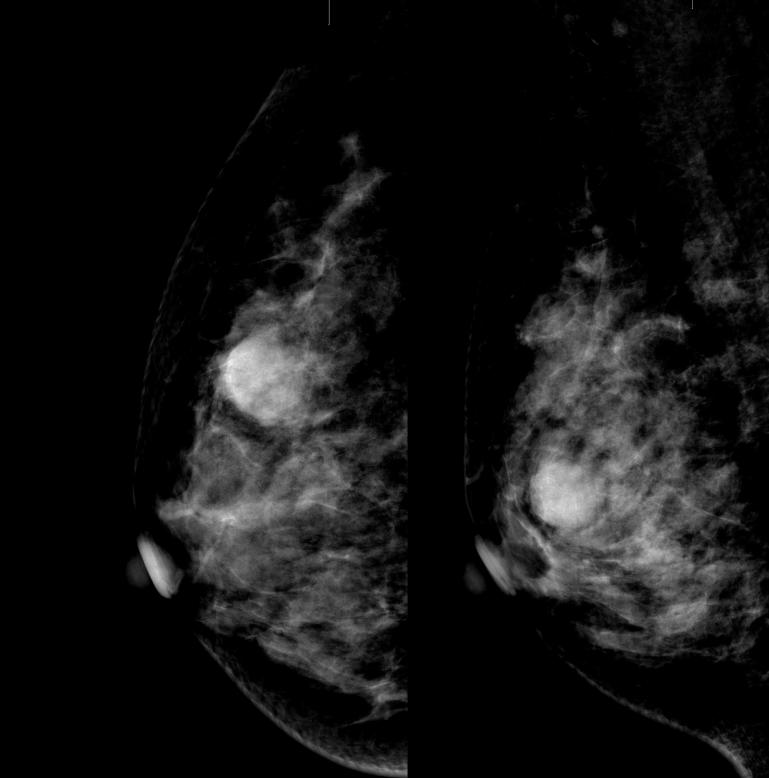

病例2:右乳段样分布短棒状、蠕虫状钙化灶

数字化摄影是什么检查好消息!助力乳腺癌早期诊断 青田人民医院数字化乳腺X线机正式投入使用_https://www.jmylbn.com_新闻资讯_第14张